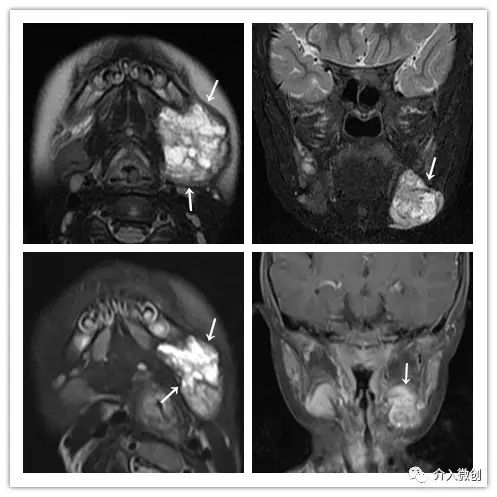

儿童颈部淋巴管畸形

颈部彩超示左颌下淋巴管畸形,瘤体内可见多发分隔囊腔。

颈部MRI示示左颌下淋巴管畸形。

DSA引导下经皮穿刺硬化注射治疗。